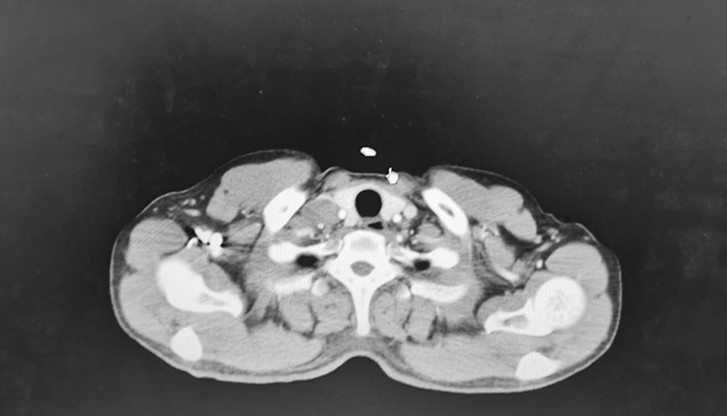

食管癌为常见的恶性消化道肿瘤,手术切除为治疗主要手段之一,但术后患者如果没能规范足疗程完成术后辅助治疗,亦可出现锁骨上淋巴结转移。对于此类患者,临床可以采用免疫检...

免疫治疗药物在食管癌二线甚至一线治疗中已经取得了令人振奋的临床疗效,人们也期待着其在新辅助治疗方面能够同样带来惊喜!本期我们将分享一例IVA期食管癌通过术前新辅助...

免疫治疗药物在食管癌二线甚至一线治疗中已经取得了令人振奋的临床疗效,人们也期待着其在新辅助治疗方面能够同样带来惊喜!本期我们将分享一例IVA期食管癌通过术前新辅助...